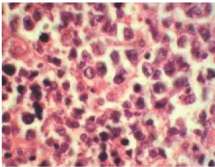

A total parotidectomy with preauricular skin incision was planned. However, intra-operatively involvement of surrounding muscles, periparotid lymph nodes and level II b / III lymph nodes was noted. Facial nerve and its terminal branches were preserved with careful dissection, however there was adherence of inferior division of facial nerve to the tumour mass which was cleared carefully under microscopic control. The retromandibular vein was ligated and a globular mass seen arising from the deep lobe of the parotid. The tumour was removed in to along with other smaller mass from the deep lobe. Total parotidectomy was performed along with excision of unhealthy overlying skin, part of upper and anterior border of Sternocleidomastoid muscle and a part of posterior belly of Digastric muscle. Level II b and III lymph node clearance was done. A suction drain was put for 48hours. Post operative recovery was uneventful with minimal deviation of angle of the mouth which recovered fully after two weeks. Histopathology of the mass revealed diffuse large B cell NHL showing sheets and strands of atypical lymphoid cells with involvement of superficial, deep lobe of parotid, Sternocleidomastoid muscle and Digastric muscle. Skin and level IIb and III lymph nodes also revealed similar population of atypical cells with perinodal extension. The tumour cells were positive strongly for CD20, LCA and CD79a on Immunohistochemistry (IHC). However, the cells were negative for CD5, CD3, EMA, CK and TdT on IHC. The Ki-67 labelling index was 100% (Figures 3-8).

Figure 7 HPE Specimen (H&E, x200) - Infiltration of salivary gland parenchyma with atypical lymphoid cells having high N: C ration and moderate degree of nuclear pleomorphism.